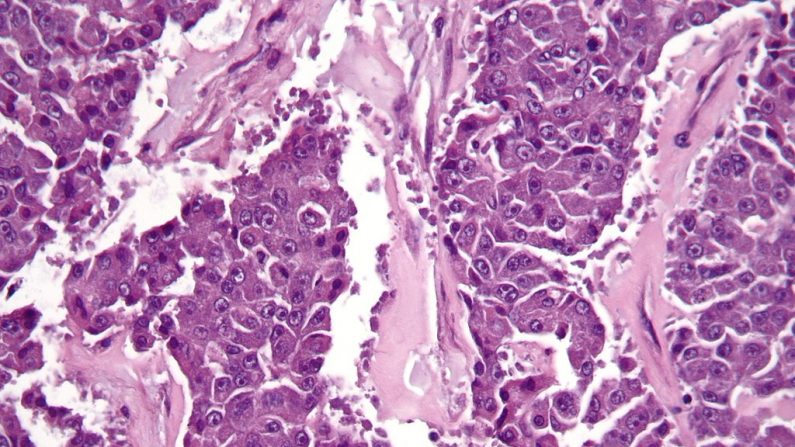

Carcinome à cellules acineuses (Nephron/Wikimedia Commons)

L’adénocarcinome canalaire du pancréas (ADP) est communément appelé cancer du pancréas et plus de 90 % des tumeurs malignes du pancréas sont des adénocarcinomes canalaires, selon le document du Comité sur les tumeurs hépatobiliopancréatiques du CHU de Donostia.